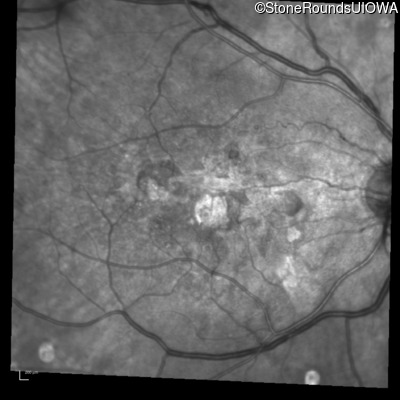

Infrared Fundus Photograph - Right - 20/250

Exemplar